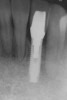

Figure 3  Preoperative radiograph of the failing implant in the site of tooth No. 22.

Figure 3